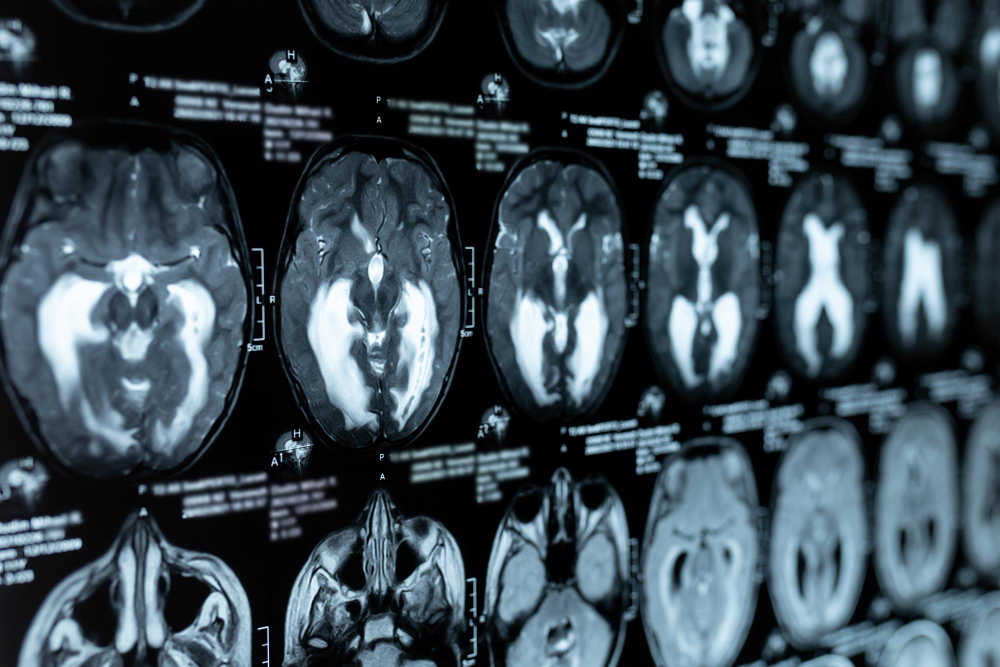

• MRI scan: Gives clear pictures of brain structures